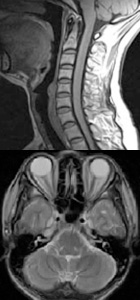

MRI(1.5T)

脳ドック

なってからでは遅い、脳卒中

脳卒中(脳梗塞、クモ膜下出血、脳出血等)は突然発症し、多くの場合何らかの後遺症を残してしまいます。最近問題となっている生活習慣病(高血圧・糖尿病・高脂血症)は脳卒中の危険因子とされており、このため普段からの生活習慣に注意し予防していくことが重要です。また一方で脳梗塞のなかには、呂律が回らない等の軽い症状であったり、潜在性に進行して認知症の原因になる場合もあります。クモ膜下出血の原因である脳動脈瘤は発症以前には気づかれず、遺伝性の発症も指摘されております。40歳を過ぎてこれらの危険因子のある方は特に脳の精密検査をお勧めします。